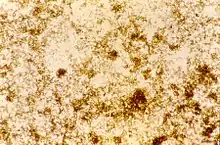

The malaria parasite, therefore, detoxifies the hematin, which it does by biocrystallization—converting it into insoluble and chemically inert β-hematin crystals (called hemozoin).[13][14][15] In Plasmodium the food vacuole fills with hemozoin crystals, which are about 100-200 nanometres long and each contain about 80,000 heme molecules.[4] Detoxification through biocrystallization is distinct from the detoxification process in mammals, where an enzyme called heme oxygenase instead breaks excess heme into biliverdin, iron, and carbon monoxide.[16]

Hemozoin crystals have a distinct triclinic structure and are weakly magnetic. The difference between diamagnetic low-spin oxyhemoglobin and paramagnetic hemozoin can be used for isolation.[33][34] They also exhibit optical dichroism, meaning they absorb light more strongly along their length than across their width, enabling the automated detection of malaria.[35] Hemozoin is produced in a form that, under the action of an applied magnetic field, gives rise to an induced optical dichroism characteristic of the hemozoin concentration; and precise measurement of this induced dichroism (Magnetic circular dichroism) may be used to determine the level of malarial infection.[36]